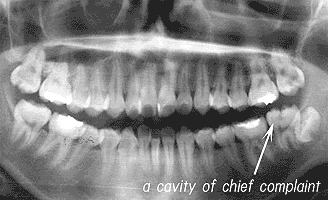

Fig. 1 CASE A The patient was 17 years old at the time of first medical examination. She visited the clinic because the cavity of the lower left tooth was causing concern. In fact the cavity of the second molar of the upper right and left are larger and in a more serious state.

Fig. 2 CASE A

Although in the case of the second molar of the upper right the nerve was removed, the three remaining cavities were packed with resin and that ended the medical treatment.

If the tooth smarted just a little about one month earlier, how about several months ago? From the outside even if nothing appears to be wrong, if an X ray is taken of the tooth a cavity which has almost reached the nerve will often be discovered. (Fig 1-2) Since there is no ache the patient does not even know of the cavity's existence. The tooth is treated and the advancement of the cavity is controlled but even for the specialist dentist it is impossible for to anticipate if there will be pain resulting from this treatment. However if the tooth is left untreated it is certain that the nerve will need to be removed within several months. Even though there is only a fifty/ fifty chance of preserving the tooth's nerve don't you think that it is better to treat with this target in mind?

CASE A. A woman who was 17 years old at the time of first medical examination.

She visited the dental clinic because the tooth at the back of the lower left side was causing concern. She could check the lower molar using a mirror relatively easily. However because the upper molars were difficult to check in the mirror development there was going on unnoticed. In fact a deep cavity which had reached the nerve was developing in the far most left and right of the upper teeth. Looking at the X ray the cavities development is obvious. Total medical treatment of the four cavities, including a small cavity in the lower right tooth, was performed. Since the upper right secondary molars had reached the nerve the dental pulp was removed.